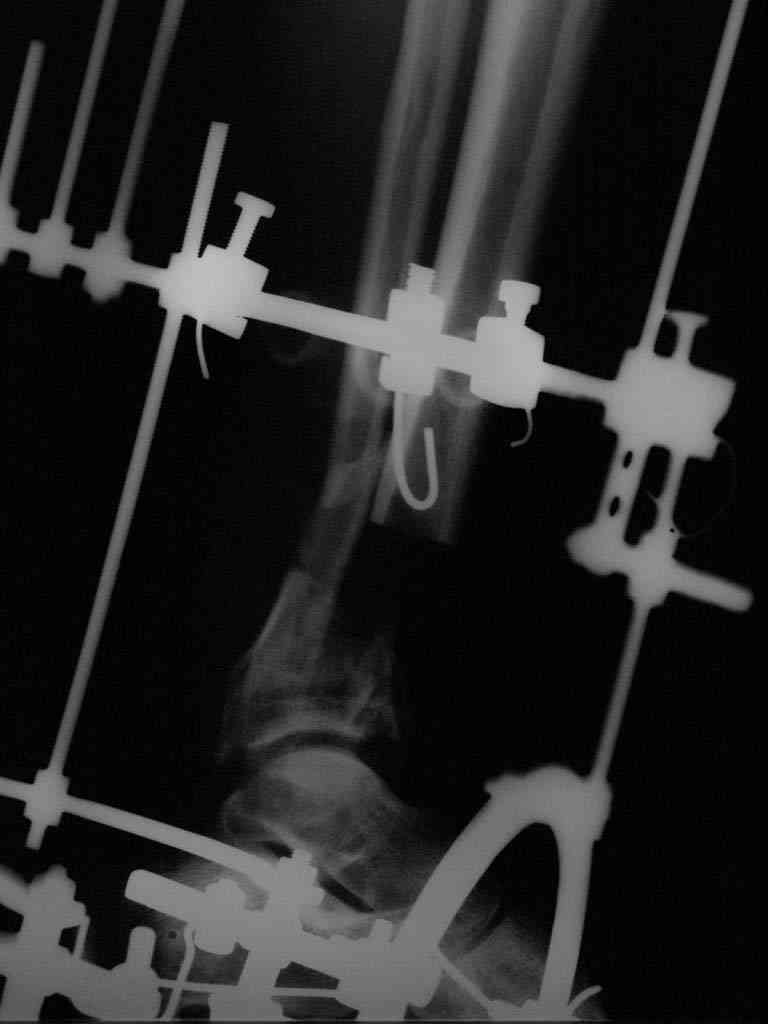

|  |  |  |  status localis на 14.11.08 (В ране визуализируется сухожилие.) | Больной А, 40 лет, находится в клинике с 15.10.08 с диагнозом: Сочетанная травма. Ушиб головного мозга лёгкой степени тяжести. Компрессионные переломы тел 12 грудного и 5 поясничного позвонков без неврологических осложнений. Закрытый внутрисуставной многооскольчатый перелом дистальных метаэпифизов обеих костей правой голени со смещением. Открытый внутрисуставной многооскольчатый перелом дистальных метаэпифизов обеих костей левой голени со смещением (см. Р-граммы). Хронический алкоголизм. Доставлен СМП после падения с 5-го этажа (не суицид). При поступлении состояние тяжелое. Глубокое оглушение. Дыхание самостоятельное, адекватное. Гемодинамика стабильная. По внутренней поверхности левой голени, в нижней трети, рвано-ушибленная рана 10-6 см, из раны выстоит проксимальный отломок большеберцовой кости, рана обильно загрязнена землёй. Интенсивная терапия в условиях реанимационного отделения, вытяжение за правую пяточную кость, параартериальная блокада обеих нижних конечностей, гипсовая лонгета на левую нижнюю конечность, ас-повязка на рану. Через 4 часа после поступления оперирован: после неоднократного промывания раны тёплой проточной водой с мылом, антисептиками, при ревизии определяется земля в канале проксимального отломка на глубину 3 см..., отсутствие надкостницы на концах дистального и проксимального отломков на 3 см. Удалено значительное количество мелких костных фрагментов, перемешанных с землёй, выполнена ПХО раны, резекция проксимального конца большеберцовой кости на 3,5 см, ЧКДО аппаратом Илизарова. Рана не ушивалась. В последующем перевязки раны с "Левомеколь", через 3 недели с момента травмы в ране определялись грануляции, нежизнеспособный конец дистального отломка. 10.11.08 ВХО раны, резекция дистального отломка на 3 см, перемонтаж аппарата наружной фиксации (см. Р-граммы). Отломки сближены на 2 см (остеотомию малоберцовой не делали). В настоящее время (5 сутки после операции) незначительное количество серозного отделяемого из раны, имеется дефект кости 4 см (см. Р-граммы). В последующем склоняемся к перемонтажу аппарата наружной фиксации, остеотомии малоберцовой кости в области повреждения, сближении отломков. По заживлению раны удлинение левой голени на 4 см. Однако, некоторыми высказывалось мнение о необходимости артродеза. Представляем рентгенограммы левой голени при поступлении, после повторного оперативного лечения и фото st.localis на 14.11.08. Будем очень благодарны за критику, комментарии, пожелания и мнения о дальнейшей тактике лечения.

Больному выполнена резекция малоберцовой кости, ВХО раны, сближение отломков. Резекция м\б через отдельный разрез. После ВХО компрессия в аппарате, края раны сближены наводящими швами (без натяжения).

В случае гладкого заживления раны, при условии положительного решения вопроса с металлом, планируем перемонтаж аппарата Илизарова, дополнительную резекцию дистального отломка, выведение полокости голеностопного сустава в правильное положение (см. боковую Р-грамму), одномоментно остеотомия большеберцовой кости. После восстановления длинны голени, по всей видимости, артродез голеностопного сустава.

Рентгенограммы прилагаются. Фото местного статуса выложу в ближайшее время.